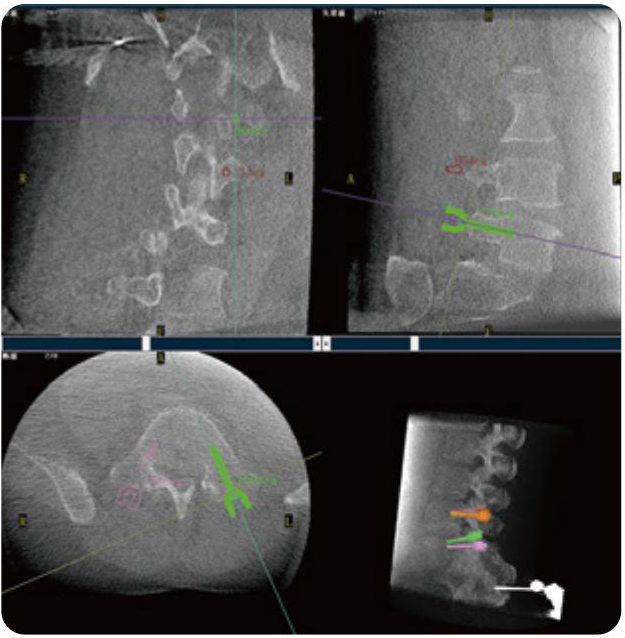

PL300B可應用于多節(jié)段脊柱外科手術,輔助醫(yī)生定位病灶部位,為脊柱外科手術(經(jīng)皮椎體成形術、椎弓根螺釘內固定術等術式)提供術前手術流程規(guī)劃、入釘位置、角度可視化引導,模擬仿真入釘輔助。